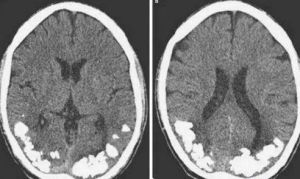

現階段醫學界對邦納綜合徵的研究有限,初步認為是患者視神經受損後,大腦用存儲畫面填補空白點的一種過度補償。